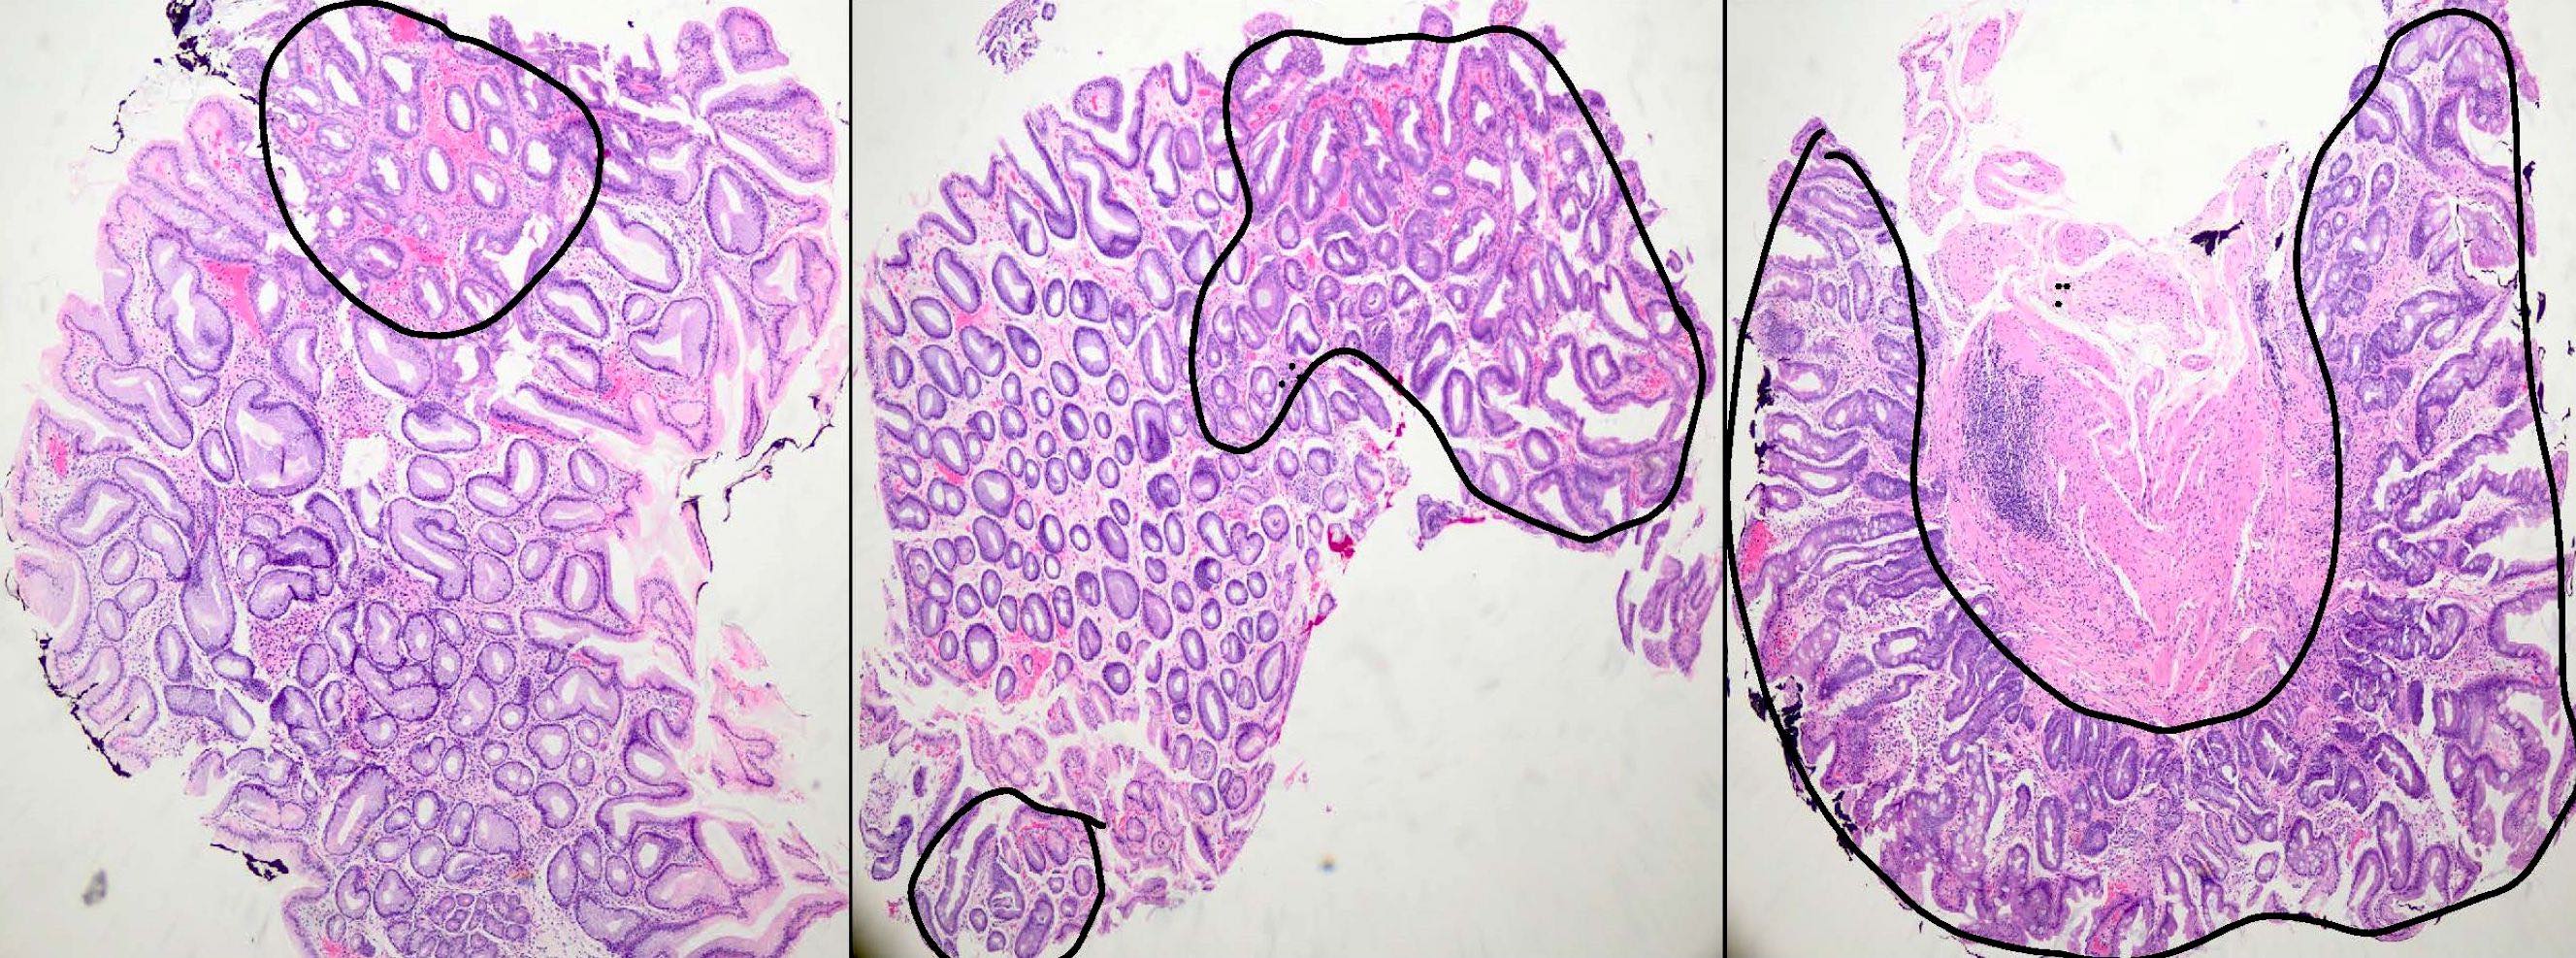

- Intestinal metaplasia can be identified by the replacement of gastric columnar mucosa with intestinal type of mucosa comprised of goblet cells, with or without Paneth cells and absorptive brush border

- Usually occurs in a background of chronic gastritis or H. pylori gastritis

- It can be classified as complete (type I) and incomplete (II and III) subtypes

- Complete (type I) intestinal metaplasia (Cancer Res 1999;59:1003):

- Resembles small intestinal mucosa with straight crypt architecture, well formed goblet cells, Paneth cells and absorptive brush border

- Incomplete (type II and III):

- Histologically resembles either small or large intestinal mucosa and shows irregular architecture, variable size goblet cells and columnar mucosa in various stages of differentiation; Paneth cells and absorptive brush border may or may not be seen

- Intestinal metaplasia is graded as mild (< 30%), moderate (31 - 60%) and marked (61 - 100%) according to the updated Sydney classification

- Intestinal metaplasia is staged using the OLGA / OLGIM system; it is based on the grades of intestinal metaplasia in the antrum (including incisura) and body

A 65 year old man presented to clinic with complaints of dyspepsia and acid reflux. An endoscopic biopsy was done and the sample was sent for histopathological examination. Based on the histopathological image above, what is the diagnosis?

- Chronic gastritis only

- H. pylori gastritis with intestinal metaplasia

- Intestinal metaplasia

- Reactive gastropathy

Practice answer #1

B. H. pylori gastritis with intestinal metaplasia. Intestinal metaplasia most commonly occurs in the background of H. pylori infection. Intestinal metaplasia can be recognized readily by the presence of well formed goblet cells.